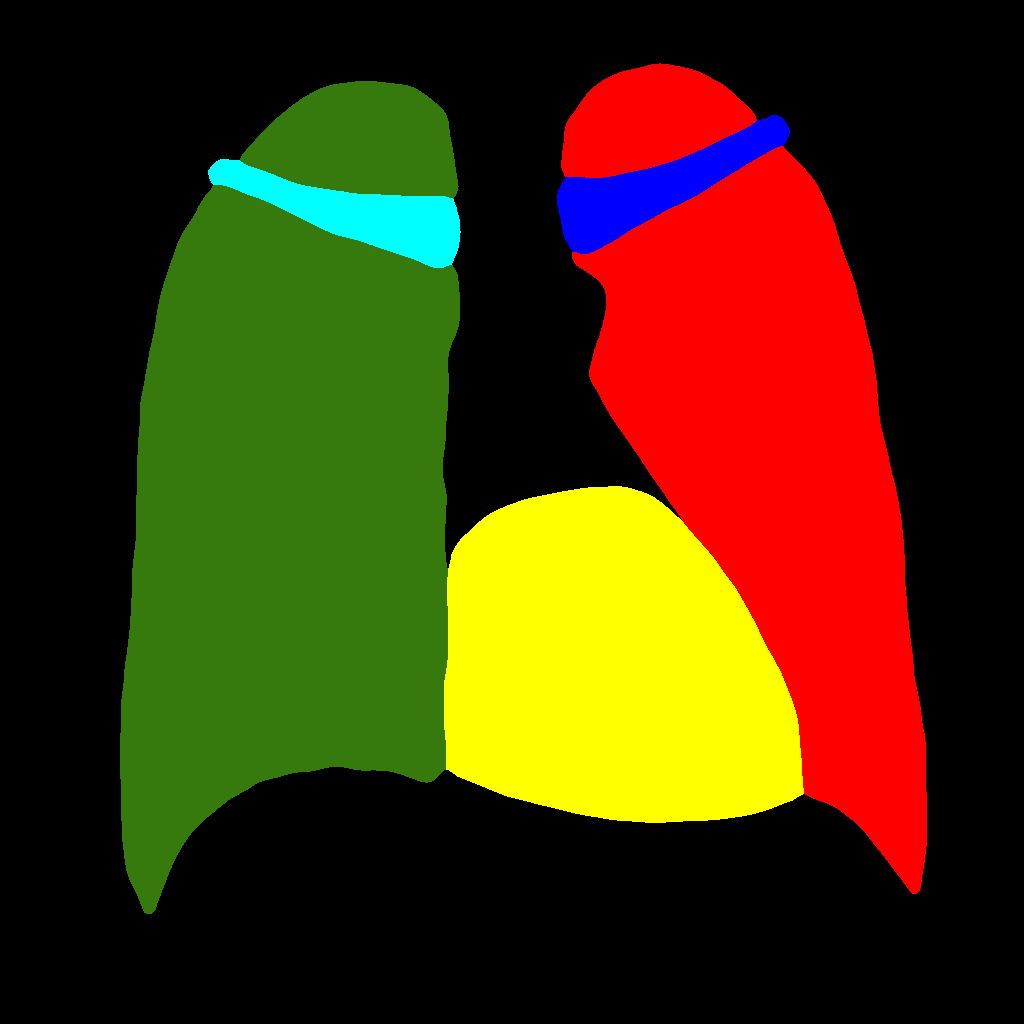

In this approach, the generation procedure is divided into two steps. The first one consists in generating the labels through a PGGAN, while, in the second, the translation from the label to the corresponding chest X–ray image is carried out, using Pix2PixHD (see Figure 2).

Figure 5 and Figure 6 display some examples — randomly chosen from all the generated images — of the label–maps and the corresponding chest X–ray images generated with the three methods described in Section 3, using the FULL_DATASET and the TINY_DATASET, respectively. We can observe that, with the single and two–stage methods, the images tend to be more similar to those belonging to the training set. For example, in most of the generated images there are white rectangles, which resemble those present in the training images, used to cover the names of both the patient and the hospital. Instead, the three–stage method does not produce such artifacts, suggesting that it is less prone to overfitting.